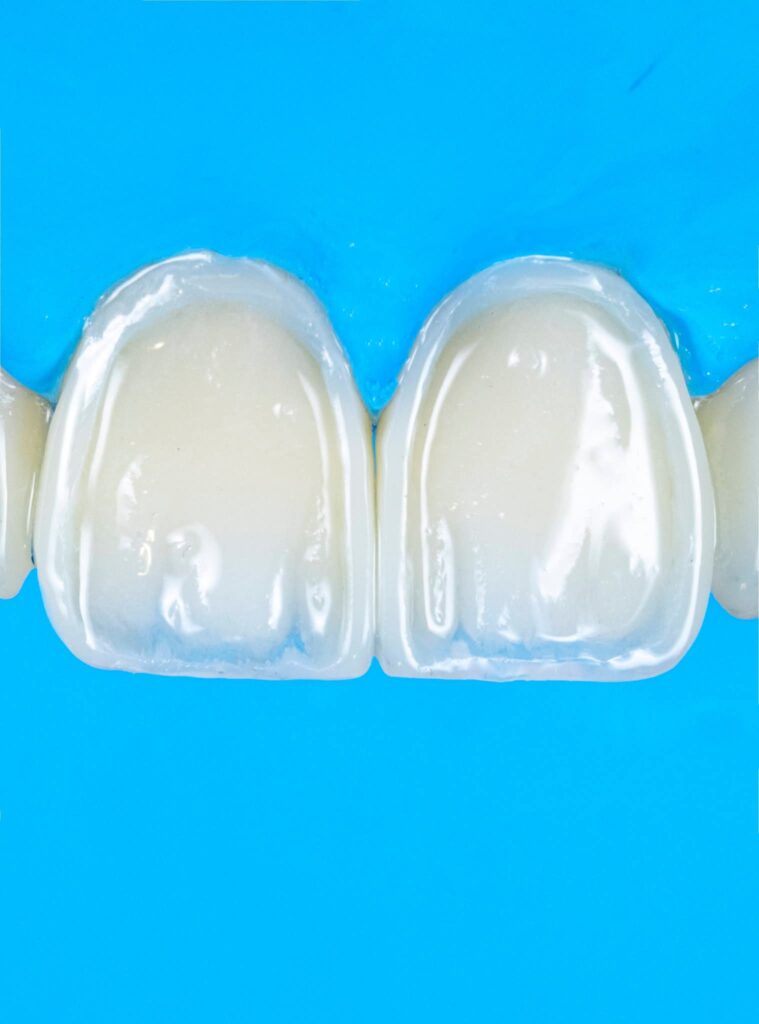

Symmetry refers to the mirror relationship between the right and left sides, especially the maxillary central incisors. Absolute symmetry is not always natural; therefore, perceived symmetry is more important than mathematical symmetry. Small differences in line angles, embrasures, and incisal edges can be used intentionally to create a natural appearance.

Proportionality relates to the width-to-length ratio and the relationship between anterior teeth. The ideal width/length ratio for central incisors is approximately 75–80%, and the apparent width proportion between anterior teeth often follows the golden proportion (~62%), although modern aesthetic dentistry prefers the concept of Recurring Esthetic Dental (RED) proportion for more natural results.

3. Surface texture and light reflection

4. Incisal translucency and halo effects